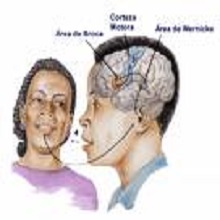

Муцање представља поремећај говора, јавља се код особа свих узраста, а значајно утиче на флуентност и временску форму говора. Муцање је повезано са разликама у анатомији мозга, функционисању и регулацији допамина за које се сматра да су последица генетских узрока. |

| Акутни мождани удар (инфаркт мозга, инсулт, шлог, мождана кап) је болест која настаје услед запушења крвног суда (акутни исхемијски мождани удар- 75-80% болесника) или прскања крвног суда и изливања крви у мозак или око мозга (акутни хеморагијски мождани удар - 20-25% болесника). |